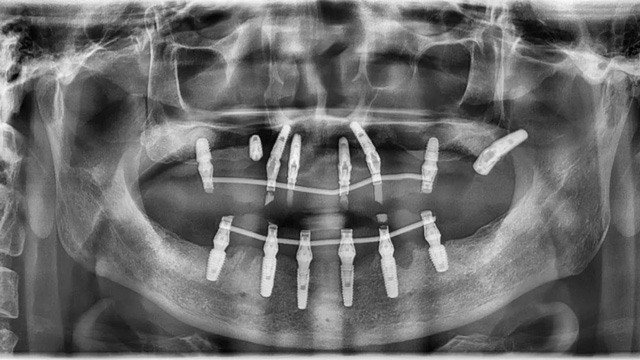

王先生全口种植后全景片(2024年4月/新桥口腔成都衣冠庙院区)

由于王先生在上一家诊所种下的6颗种植体比较短小,在力学方面达不到修复标准,还有两颗因为松动和颈部暴露无法使用,李阳军医生又加种了3颗更长更粗的,以确保长期稳定性。由于骨量不足,有两颗采用了倾斜植入以增加骨接触的面积,目的也是为了更加稳固,还有一颗因为原位置骨量太差,改为在其他位置种植,采取了高难度的术式。